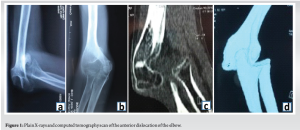

A 16-year-old Koranic student, with no past medical history, who presented at the outpatient department with a closed injury to the left elbow resulting from a fight 3 months ago, during which his forearm was allegedly twisted. The exact mechanism was poorly elucidated. Elbow radiographs revealed an anterior elbow dislocation, with no associated fracture, with ossifications along the triceps brachii tendon.

Elbow radiographs revealed an anterior elbow dislocation, with no associated fracture, with ossifications along the triceps brachii tendon (Fig. 1).